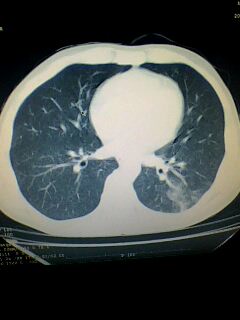

标题: CT28315:咳嗽咳痰咯血半月并胸痛 [打印本页]

标题: CT28315:咳嗽咳痰咯血半月并胸痛

1、纵膈窗效果不好,初步考虑左肺下叶感染性病灶,建议正规抗炎治疗后复查   2、右肺下叶陈旧性病灶伴局部胸膜增厚。

考虑左肺下叶周围型肺癌.图象欠清,请问病人贵更?

考虑左肺下叶周围型肺癌.

图像资料欠清,建议强化,考虑周围型肺癌。

左下肺肿块影,深分叶,考虑肺癌。

左下肺球形病灶,考虑:1:球形肺炎;2:周围型肺癌不除外,建议治疗后复查

不排除左肺下叶周围型肺癌可能!建议穿刺活检!

考虑左肺下叶周围型肺癌。

考虑左肺下叶周围型肺癌并阻塞性肺炎。

考虑左肺下叶周围型肺癌